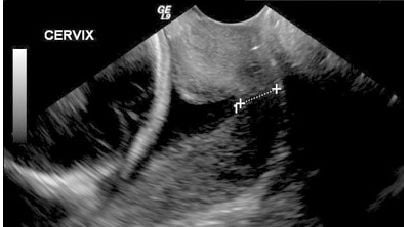

Cervical Length Assessment

The median cervical length at 20 weeks is 42mm, the 1st centile is 23mm. There appears to be value in linking shortened cervical lengths with an increase in the risk of preterm delivery.Cervical lengths of 30mm (10th centile), 27mm (5th centile) and 22mm (2.5th centile) gave relative risks of preterm birth prior to 37 weeks of 3.8, 5.4, and 6.3, respectively, with even greater relative risk at earlier gestations If a transabdominal ultrasound is undertaken and the c...